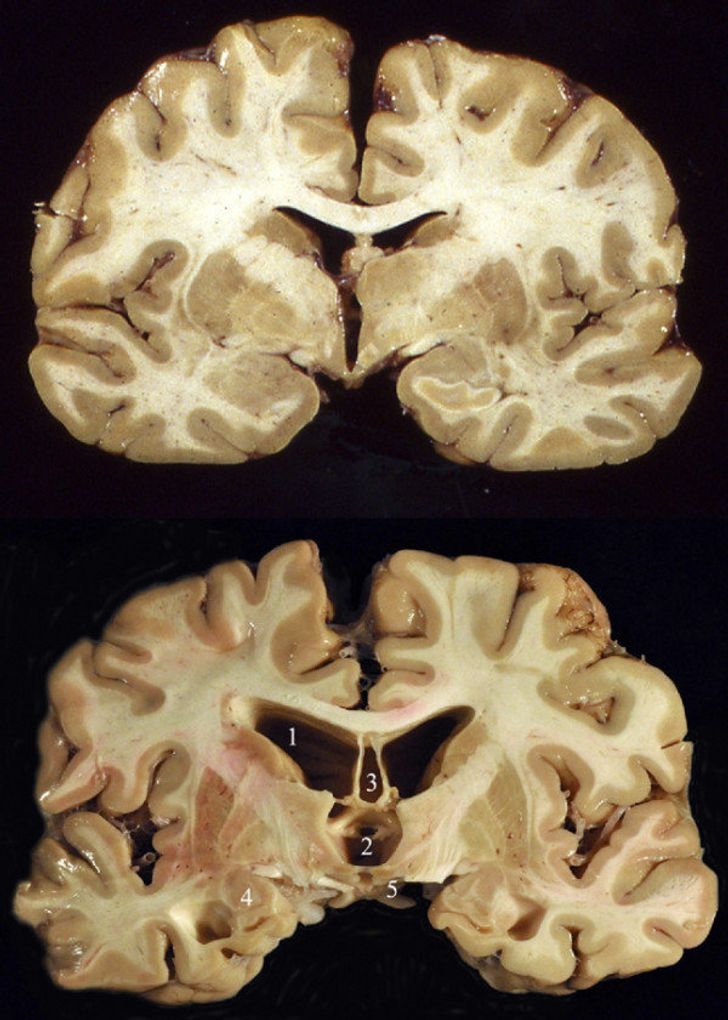

Розріз нормального людського мозку (вгорі) і мозку колишнього гравця в американський футбол (внизу)

Нижня частина мозку належала футболісту, який в останні роки свого життя страждав хронічною травматичною енцефалопатією – нейродегенеративним захворюванням, яке пов’язане з повторюваними ударами по голові.